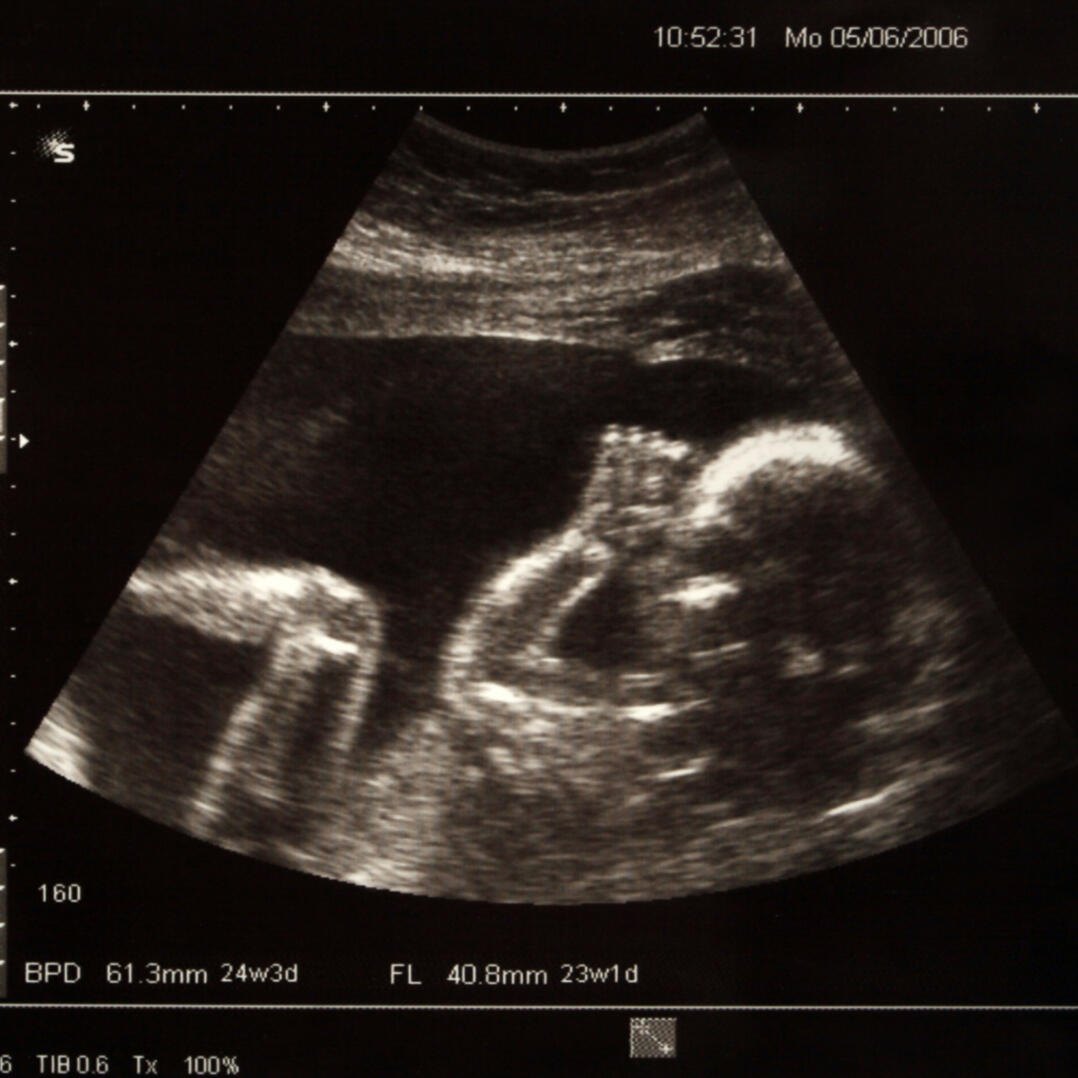

Prenatal Homicide

Abortion

We will fight until we outlaw abortion and hold all those guilty of prenatal homicide guilty.